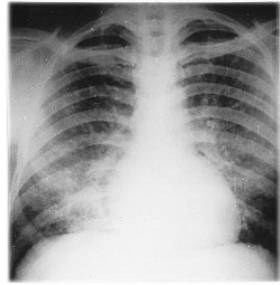

La neumonía viral o neumonitis es una complicación grave potencialmente fatal, no es frecuente en niños a menos que estén inmunocomprometidos, pero es la complicación severa más frecuente en adultos (se presenta en hasta el 20% de los adultos) ( 3, 6, 8, 9), particularmente entre fumadores (6). Suele aparecer unos días después de la aparición del exantema y (2) en ocasiones pasa inadvertida, ya que puede cursar asintomática y revelerse sólo por la radiografía de tórax. (2, 6) En contraste con la pobreza semiológica respiratoria, la radiología pulmonar muestra afección bilateral extensa, más evidente en los hilios y los campos inferiores; el infiltrado es típicamente intersticio-nodular; pero en algunos casos se calcifica, dando lugar a un patrón miliar permanente. (2, 6) En los casos graves se manifiesta por tos, hemoptisis, cianosis, taquipnea, dificultad para respirar, fiebre, y dolor torácico al respirar. (6, 9)